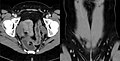

Media in category "Muscles of the human torso"

The following 90 files are in this category, out of 90 total.